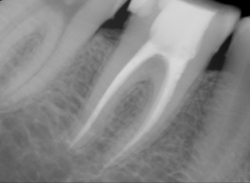

Root Canal, X-Ray on completion & Process Photo

(white space in X-Ray is treated area)